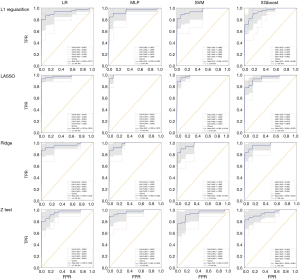

Performance of CT radiomic model in differentiating between COVID-19 and CAP

Sixteen models were established in this study. For each model, the evaluation metrics were AUC, the area under the precision-recall curve (AU-PRC), sensitivity (SEN), specificity (SPEC), F1-score, and accuracy (ACC). Table 4 summarizes the varying performance of each model for each classifier concerning the different feature selection methods. Among all the models, the Lasso regression yielded higher AUC values for all used classifiers. Notably, the MLP classifier obtained the highest AUC of 0.990 [95% confidence interval (CI): 0.962–1.000]. The results indicated that combining the LASSO with the MLP classifiers resulted in the best-performing model with the highest ACC (96.3%), SEN (95.7%), SPEC (98.4%), and AU-PRC (0.942) (Figure 3).

Full table

Conventional radiomics models were developed and evaluated concerning different feature selection algorithms and classifiers to identify COVID-19. Among the 16 different combinations, Lasso regression with MLP was the most predictive classifier with an AUC of 0.990 (95% CI: 0.962–1.000). This predictive accuracy was comparable to the DL models proposed by Li et al. (AUC =0.96 for COVID-19) and Song et al. (AUC =0.98 at the image level and 0.99 at the patient level) (7,21). Unlike the DL CAP algorithm, which requires a significant amount of labeled data for training and validation, our proposed model enabled binary classification using features derived from DL-based segmentation masks reviewed by humans. The involvement of a human factor maximizes the success of developing algorithms powered by DL in radiology.